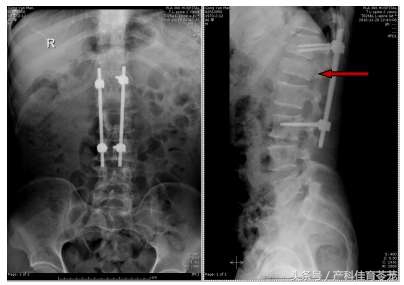

飞机到达北京国际机场后,急救车第一时间将公某送至306医院急诊。听闻患者为外出务工人员,受伤后专程回国治疗,骨科医生仔细查体,发现公某双下肢肌力0期,触痛觉减退,肛门反射消失,考虑为脊髓损伤,由于公某回国时未带任何原始医疗资料,立即安排检查。CT、X线检查结果让医护人员吓了一跳!

手术选择了错误的减压位置和固定节段,既没有解除神经压迫,也没有有效固定脊柱骨折(红箭为骨折椎体)。